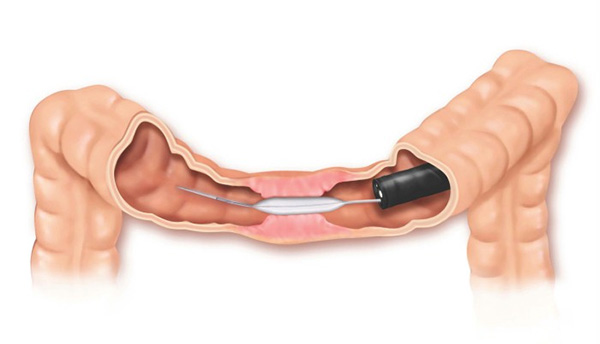

- Dilatadores flexíveis: uma série de sondas graduadas (espessura crescente) chamadas de sondas termoplásticas podem ser usadas. Estes são tubos que passam através do esófago para o estômago. Os tubos utilizados tornam-se progressivamente maior, até que o tamanho desejado seja atingido

- Balões dilatadores: a dilatação do esôfago pode ser feita usando balões durante a endoscopia. A endoscopia flexível permite ao examinador visualizar diretamente a estenose. Um balão é introduzido pelo canal do aparelho até a zona de estreitamento. Ele é então insuflado com água até uma certa pressão, que é pré-ajustada para uma dada circunferência. Quando insuflado, torna-se em forma de salsicha, esticado, e faz com que a estenose se abra.

- A Acalasia requer um tipo de balão específico, mais longo e maior, chamado de balão pneumático. Nesta situação, as fibras musculares espásticas na parte inferior do esôfago são esticadas.

Dilatação do esôfago é a técnica utilizada para esticar uma parte bloqueada ou estreitada do esôfago. Este procedimento é usado quando uma parte do esôfago tornou-se tão estreita que se torna difícil, ou mesmo impossível e doloroso para engolir.